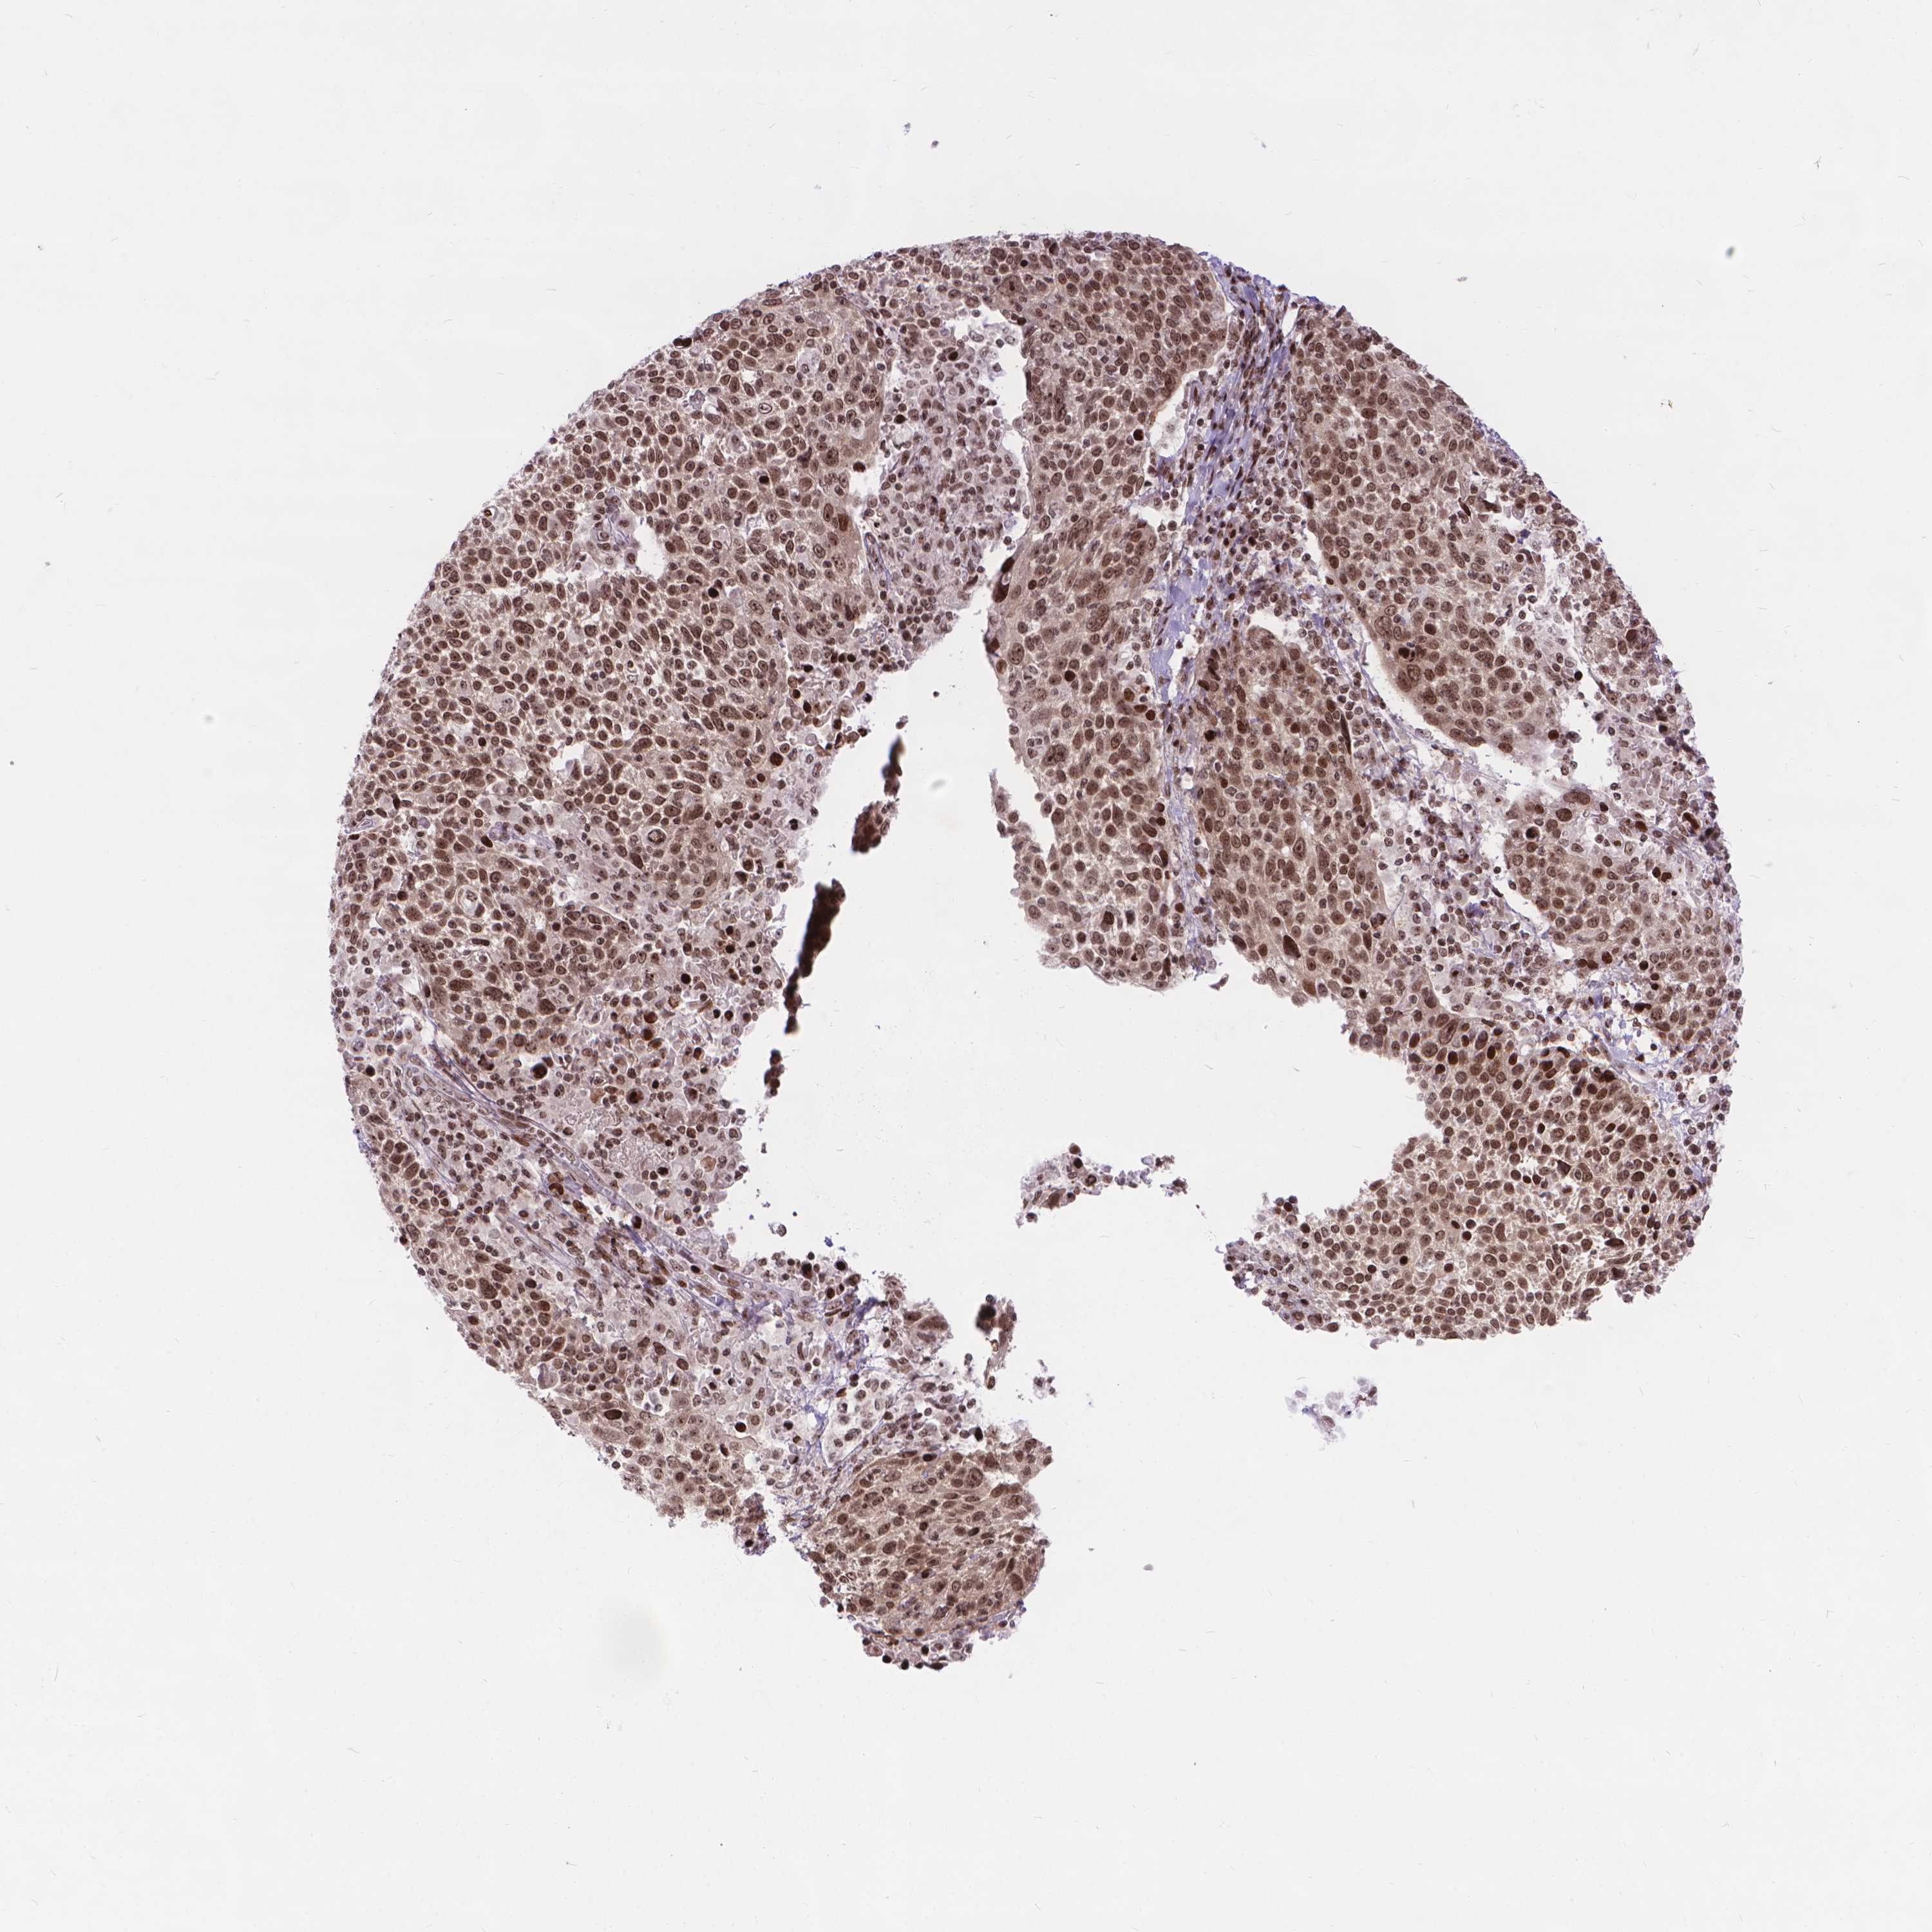

CERVICAL CANCER - Protein expressioni

A mouse-over function shows sample information and annotation data. Click on an image to view it in a full screen mode. Samples can be filtered based on level of antibody staining by selecting one or several of the following categories: high, medium, low and not detected. The assay and annotation is described here.

Note that samples used for immunohistochemistry by the Human Protein Atlas do not correspond to samples in the TCGA dataset.

Antibody stainingi

Antibody staining in the annotated cell types in the current human tissue is reported as not detected, low, medium, or high, based on conventional immunohistochemistry profiling in selected tissues. This score is based on the combination of the staining intensity and fraction of stained cells.

Each image is clickable and will lead to virtual microscopy that enables deeper exploration of all samples and also displays staining intensity scores, fraction scores and subcellular localization as well as patient and tissue information for each sample.

Antibody HPA065214

Staining

High

Medium

Low

Not detected

Intensity

Strong

Moderate

Weak

Negative

Quantity

>75%

75%-25%

<25%

None

Location

Nuclear

Cytoplasmic/membranous

Cytoplasmic/membranous,nuclear

Squamous cell carcinoma, NOS

Adenocarcinoma, NOS